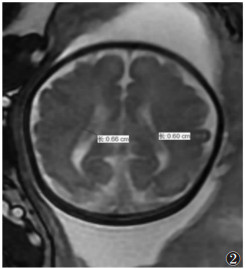

使用1.5 T Philips MRI B-TFE快速扫描技术进行扫描。扫描序列和参数:二维快速稳态进动序列和单次快速自旋回波序列,TR 3.5~5.0 ms,TE 1.5~1.8 ms,翻转角5°~60°,带宽125.00 Hz/像素,矩阵236×236或256×256,采集次数2次,层厚4~6 mm,间隔1 mm,FOV 36 cm×36 cm。胎儿头颅横断位及冠状位扫描须在出现完整胎儿形态的基础上再依据胎儿的矢状位重新定位扫描,须在上一个序列扫描完成的基础上进行,在侧脑室水平(脉络丛视野良好)测量[6]图 12)。

图 2 胎儿头颅MRI扫描的横断面,测量侧脑室的直径